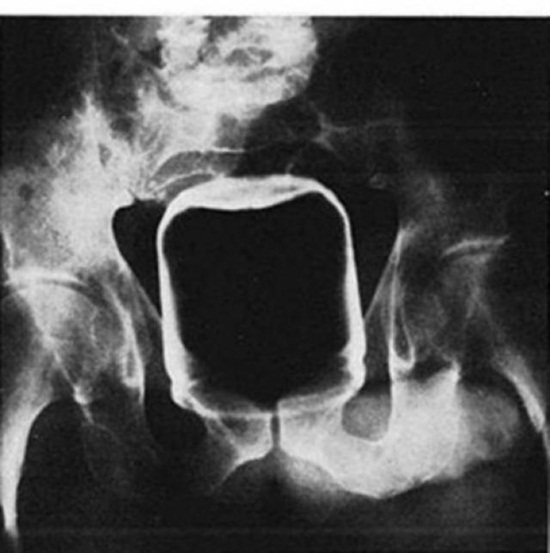

ขวดแชมพู